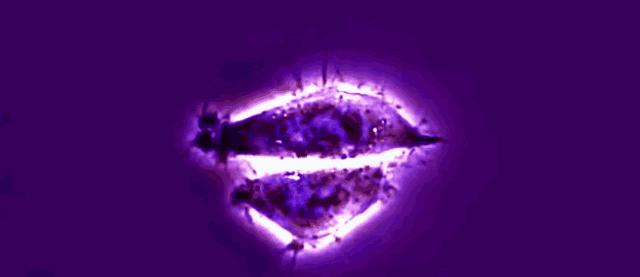

电镜下的海拉细胞

拉克斯从入院检验之时就受到了盖的高度关注

因为她的肿瘤形态与一般的宫颈癌肿瘤有着

很显著的差异。通常宫颈癌肿瘤呈现像菜花

一样不平整的形貌。但拉克斯的肿瘤却像个

紫色的葡萄一样光滑,稍微一碰就会出血